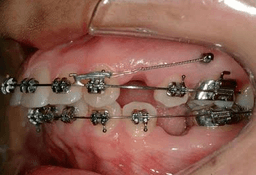

Mini Screw Assisted Treatment

Advanced orthodontic technique using temporary anchorage devices (TADs) to achieve complex tooth movements that were previously difficult or impossible. Mini screws provide stable anchorage without relying on patient compliance.